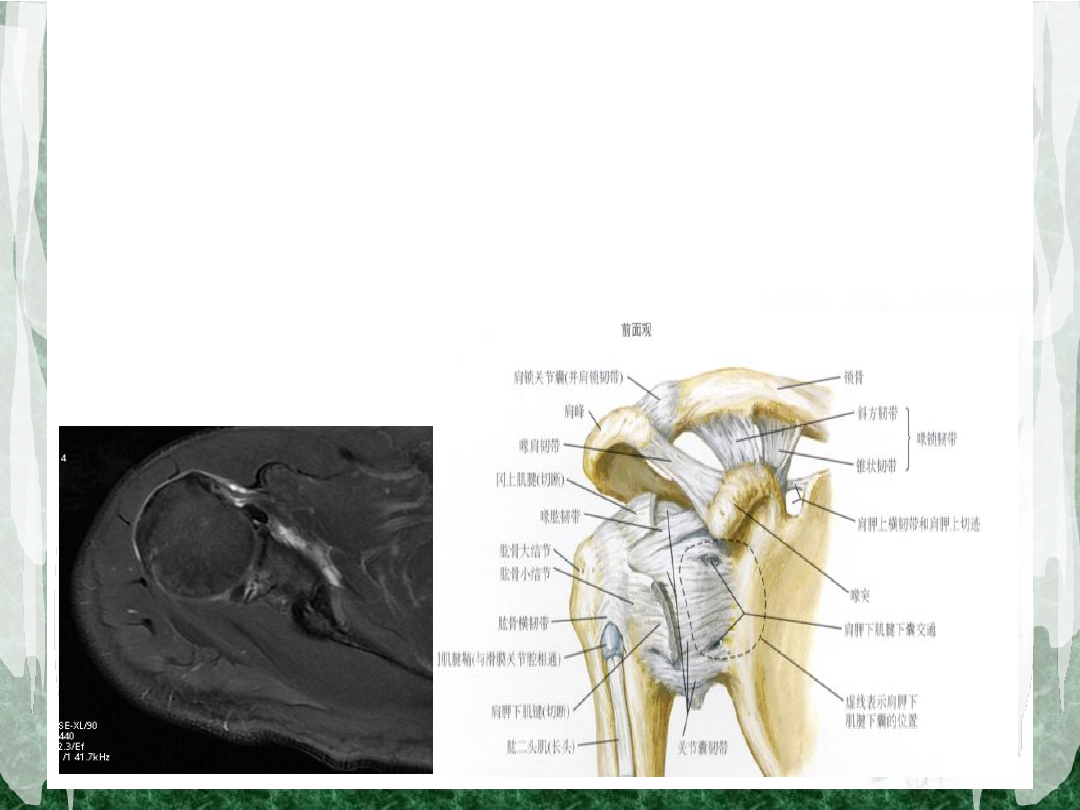

肩关节的功能解剖

个关节组成:胸锁关节、肩锁关节、盂肱关节、肩胛

胸壁关节。

盂肱关节:由肱骨头

及肩胛关节盂组成,

是典型的球窝关节。

结构特点

关节盂小而浅,边缘附有盂唇

关节囊薄而松弛(薄弱区:缺少肌肉及肌腱增强

的关节囊前下部)

囊内:肱二头肌长头腱通过